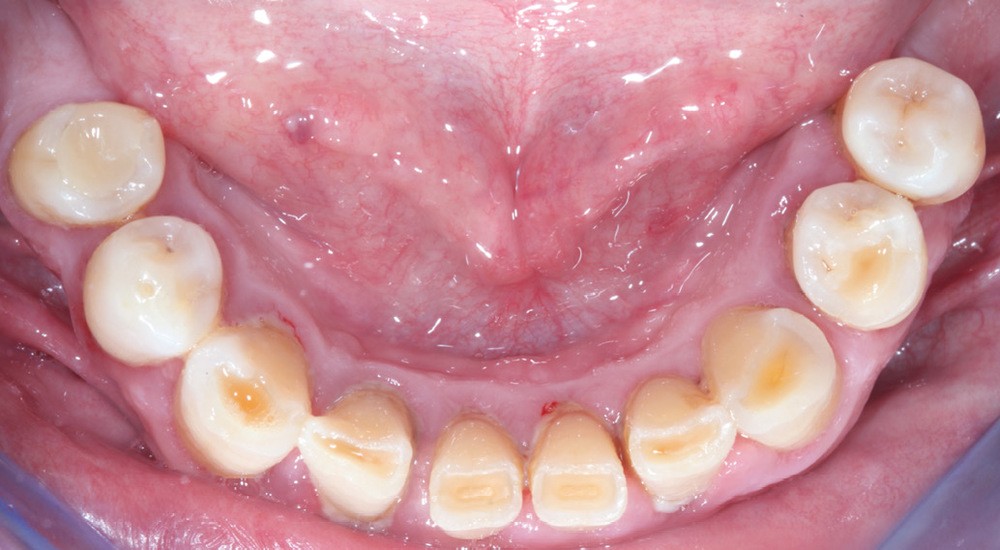

Première décision thérapeutique (janvier 2019) (fig. 1 à 3)

Après une étude prothétique [4, 5], il est décidé de procéder à l’extraction des dents maxillaires résiduelles (sauf une molaire qui servira pour enregistrer l’occlusion et qui sera avulsée dans un second temps), avec une implantation immédiate de 6 implants maxillaires et une mise en charge immédiate d’un bridge provisoire. Les implants se distribuent sur l’arcade ; des aménagements sous-sinusiens ne sont pas nécessaires (fig. 4 à 6).

Des implants mandibulaires postérieurs sont également programmés dans la même séance.

La réhabilitation bi-maxillaire est envisagée selon le concept de l’arcade courte, intéressant jusqu’aux premières molaires. La prise en charge a débuté par une motivation à l’hygiène, et une explication des techniques de prophylaxie, avec notamment la remise d’une brosse à dents électrique et des têtes de brosses adaptées et des brossettes interdentaires de tailles différentes (fig. 7).